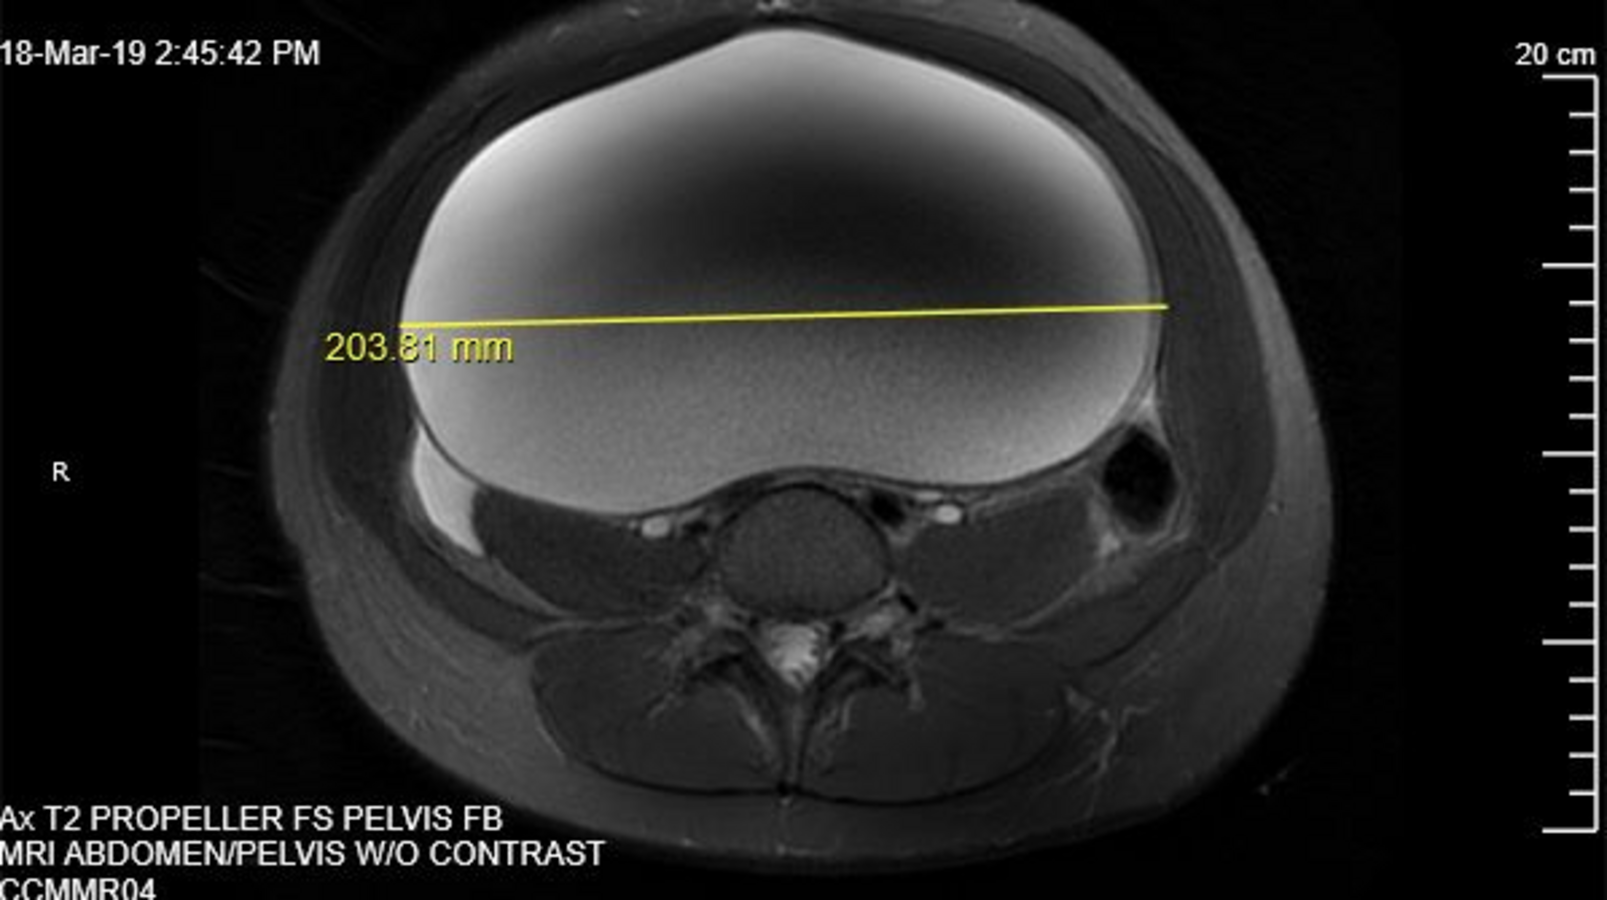

The mass appeared as a unilocular cyst with smooth contours, suggesting a benign etiology (Figures 3 and 4). No evidence of acute urinary or bowel obstruction was noted. A chest radiography scan was also conducted, results of which did not show evidence of metastatic disease. Ovary-sparing surgical excision of the cyst was conducted. The patient’s post-operative course was uneventful, and she was discharged home on post-operative day 2.